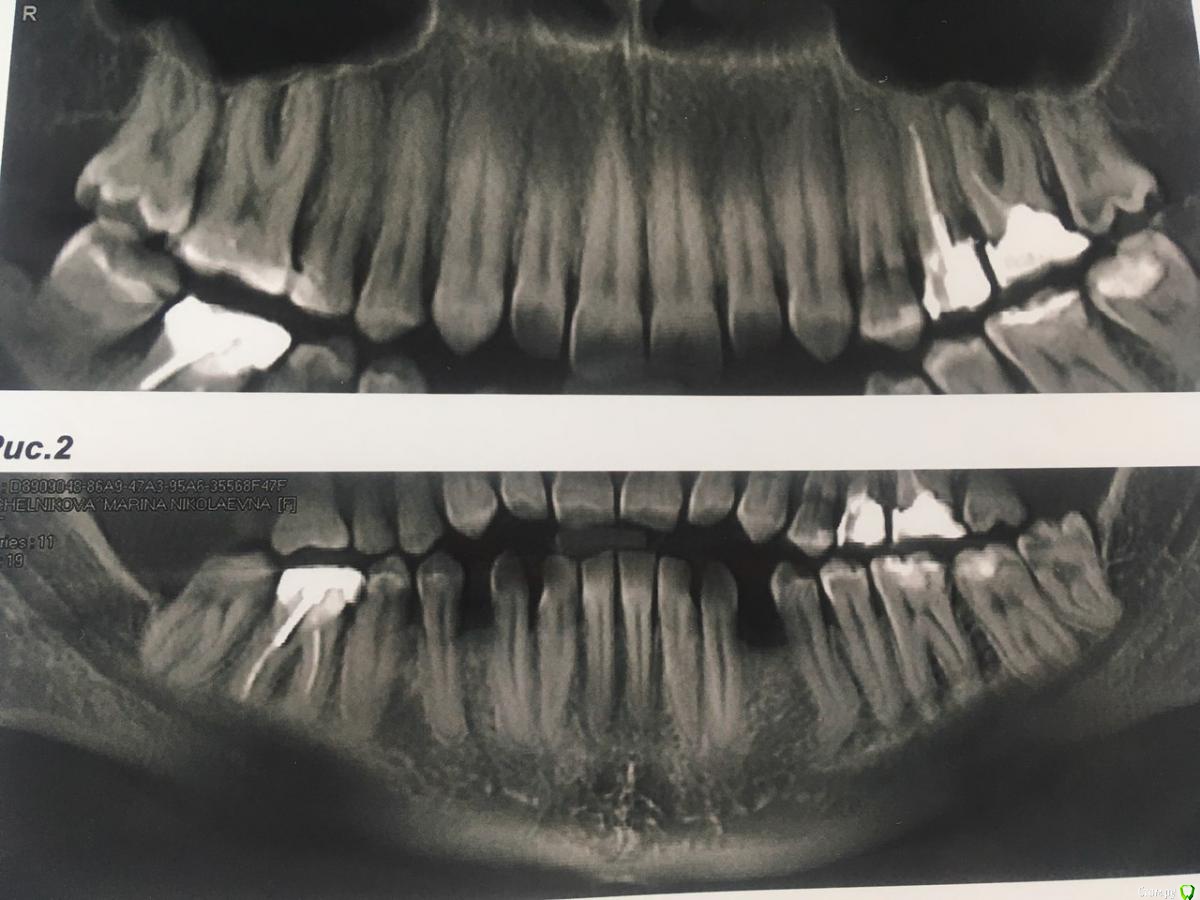

И вот уже несколько лет нижняя 6-ка периодически ноет (особенно если остыть),каждый год ходила  к одному хирургу,готовясь  уже удалить этот источник неприятных ощущений, но каждый раз врач делая р.снимок говорил все нормально.

В течении  года от зуба опустилась десна и там проглядывается прозрачно-черный корень и очень быстро на 5 и 4-ки обазовались черные пятна.  Сделала КТ. Теперь стоит вопрос долгое  лечение или удаление.Врач говорит все будет видно при вскрытии. Если лечение то долгое и без гарантий.   Мне кажется от корня там мало что осталось,судя по цвету и по тому как быстро испортились рядом стоящие зубы. Может проще не лечить,установить имплант?

Правда один врач сказал,что то вроде убыли костной ткани и имплант удержать будет не чем,кроме того сужение верхней челюсти, рецессия десны и стирание в пришеечной области из за прикуса. В заключении кт -пародонтопатия легкой степени тяжести.

соглашусь, решение нужно принимать после оценки объема оставшихся твердых тканей и перспективы протезирования. Если судить только по снимкам, то скорее удалять...